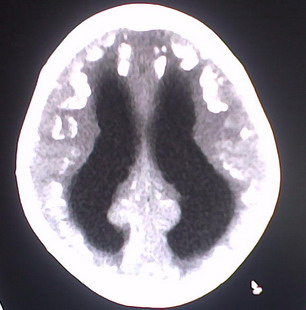

以下是引用jiajie在2009-2-3 20:02:00的发言:[br]脑室周围白质区可见大量斑片状钙化,部分融合成带状,双侧侧脑室及第三脑室扩大。[br]考虑弓形体原虫感染。(先天性宫内感染、torch综合症)

以下是引用lkc8963在2009-2-3 21:15:00的发言:[br]临床眼睑可见静脉扩张,ct双侧眼上静脉亦示扩张,颅内钙化以皮层\\软脑膜为主而不是位于白质和室管膜,再加上静脉窦异常,还是应该考虑静脉血管瘤病,可能为较复杂的血管畸形.

以下是引用卜一在2009-2-4 9:21:00的发言:[br]sturge-weber综合征:面部三叉神经分布区的毛细血管性或海绵状血管瘤以及同侧枕、顶或额叶软脑膜的血管瘤(以静脉性为主)。脑皮质,特别是第二三层,毛细血管可有增厚和钙化。局部发生层状坏死、神经细胞脱失、萎缩、胶质细胞增生及钙盐沉着。可根据面部典型分布的特征性皮痣作出诊断。头颅ct:发现面部血管瘤同侧的脑内病理钙化影,呈双层线条波浪形、脑回形或树枝形。本例支持:sturge-weber综合征![br]